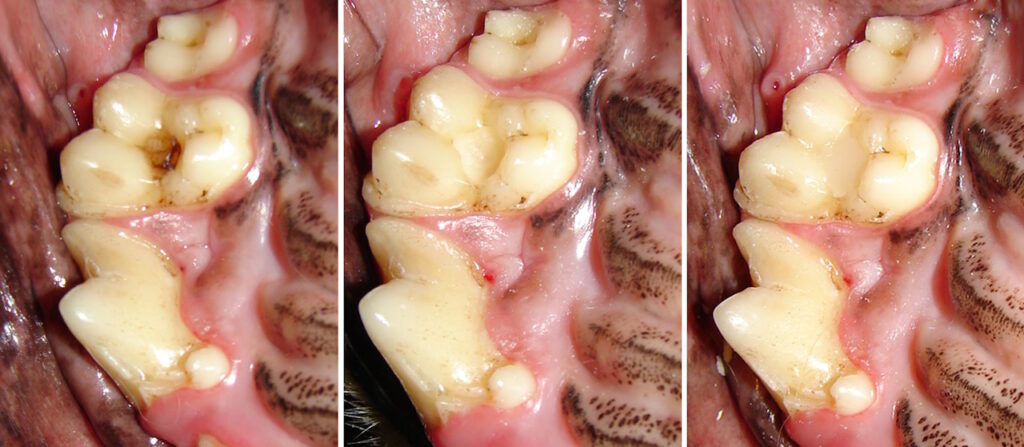

A small enamel defect is present on the outside surface of the lower first molar tooth in a dog.

The defect is prepared and filled with composite filling material.